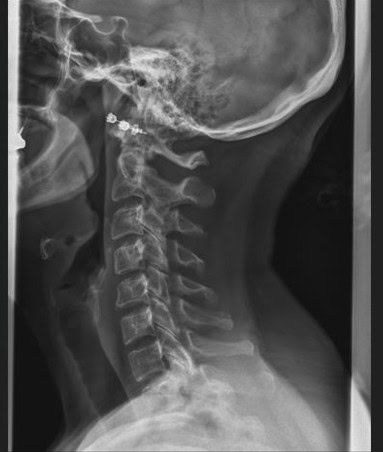

Post Scan